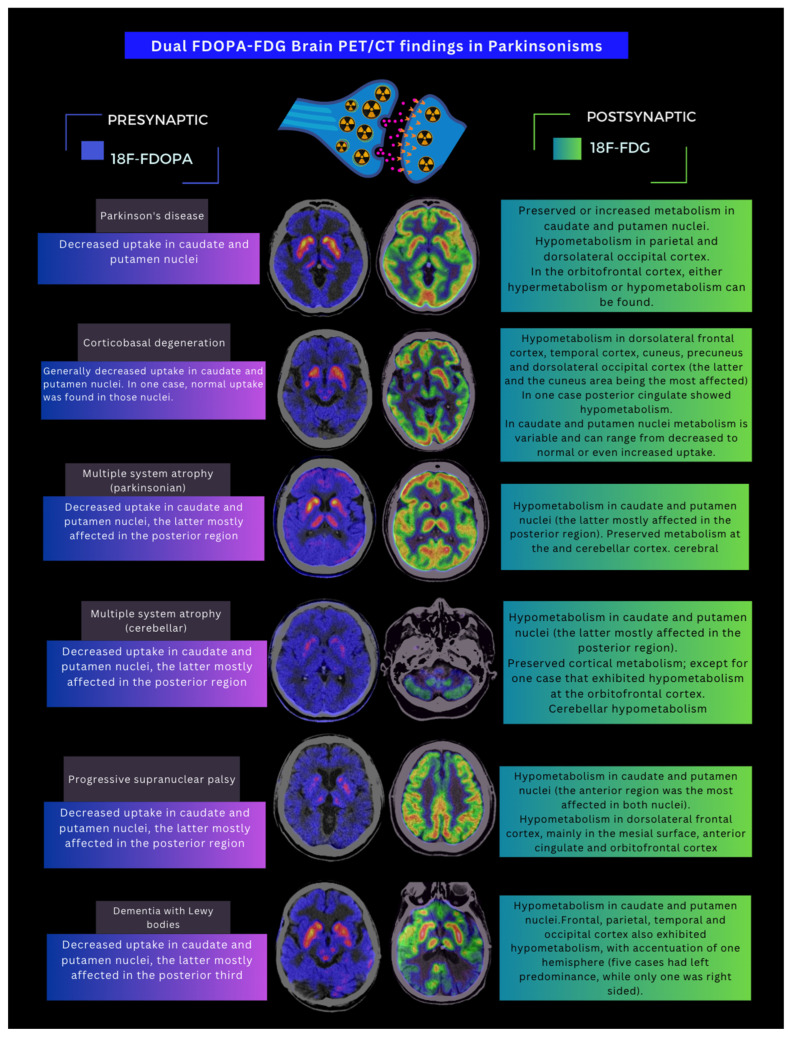

Among the 150 patients, 149 (99.3%) exhibited abnormal findings on FDOPA PET/CT. The most common abnormality observed was a reduction in uptake in the posterior third of the putamen nuclei, which occurred in 89.9% of cases. Only one patient had normal FDOPA PET results, with both clinical diagnosis and dual PET/CT suggesting DLB. An asymmetrical uptake pattern was the most common, seen in 65.1% (n = 97) of cases. Among the different Parkinsonisms, MSA-C was the only diagnosis that displayed both symmetrical and asymmetrical patterns. The asymmetrical pattern was most common in MSA-P (Scheme 1).

3.3. Brain [18F] FDG PET/CT Findings

Disturbances in glucose metabolism were observed in 47.33% of the patients. Normal metabolic findings were more frequent in patients diagnosed with PD, where overall normal cortical metabolism was observed alongside normal or hypermetabolism in the basal ganglia and hypometabolism in the parietal, occipital dorsolateral, and orbitofrontal cortex. In patients with atypical Parkinsonisms, metabolic alterations primarily affected the basal ganglia, with almost all cases presenting hypometabolism, except for DLB, where hypermetabolism in the striatum nuclei was also documented (Scheme 2).

3.4. Dual FDOPA–FDG PET/CT Diagnosis

The most frequent diagnosis provided by dual PET/CT was PD, identified in 67% (n = 101) of the patients. The remaining 33% were diagnosed with atypical Parkinsonisms: PSP in 10% (n = 15), DLB and MSA-P in 7% (n = 10) each, MSA-C in 5.33% (n = 8), and CBD in 4% (n = 6). The findings from FDOPA and FDG PET scans are summarized in Figure 1.

In 2021, the study conducted by Xian et al. [ref. 10] investigated the analysis of a coregistered set of dual PET/CT images with FDOPA and FDG in the differential diagnosis between PD and MSA-P, compared to healthy individuals, demonstrating the crucial value of the dual method in this aspect, which is perhaps the clinical scenario that represents the greatest diagnostic challenge. In our cohort, dual PET/CT changed the clinical diagnosis from PD to MSA-C in six patients and to MSA-P in seven patients; it also changed the clinical diagnosis from MSA-P to PD. This information offers exceptional value for better classifying these patients, with the goal of establishing a more accurate prognosis and, consequently, providing better treatment and follow-up. (Figure 2, Figure 3 and Figure 4).

When analyzing the findings of PET/CT per radiopharmaceutical, we found that, regarding FDOPA, 149 out of 150 patients presented some type of alteration in the presynaptic dopaminergic pathway, with a greater defect in the posterior third of the putamen (89% of cases); the most frequent pattern was asymmetrical in 64.7%. The only Parkinsonism that exhibited a symmetric uptake defect pattern was MSA-C; on the other hand, only one patient with a clinical diagnosis of DLB showed integrity in the presynaptic dopaminergic pathway, although the uptake pattern on FDG PET was consistent with that of the clinical diagnosis. In 2020, Stormezand and collaborators reported data that supported the findings of decreased uptake on FDOPA PET in both idiopathic PD and atypical Parkinsonisms, with predominance in the posterior third of the putamen [ref. 20].

Nurmi and Brousolle reported in different studies that PD first shows alterations in the posterior putamen, followed by the anterior putamen and caudate nuclei, involving the side contralateral to the clinically affected one [ref. 23,ref. 24]. In our cohort, all PD patients presented a presynaptic dopaminergic pathway alteration; according to the literature, up to 10–20% of clinically diagnosed PD cases have shown integrity of the presynaptic dopaminergic pathway when evaluated by PET [ref. 25]. This situation can also occur with DLB, in which a study demonstrates that integrity of the presynaptic dopaminergic pathway does not rule out the diagnosis [ref. 26]; this is similar to the example mentioned above, where the diagnosis was established by the altered pattern in cerebral glucose metabolism, highlighting the importance of dual studies when clinical suspicious is high.

It has been described that in MSA-P, the pattern of decreased uptake with the FDOPA tracer is primarily evident in the caudate nuclei and anterior putamen [ref. 27]. This information differs from our findings, where, as mentioned earlier, the posterior putamen was the most affected. In the case of CBD, the alteration of the striatal nuclei on the side opposite to the clinically affected hemibody has been described [ref. 28], similar to our findings. Normal findings have also been reported; however, in our study, we did not have any normal findings in this pathology.

Regarding FDG PET/CT findings, 52.67% of patients showed preserved metabolism, which can be explained by the fact that most patients had a clinical and dual PET/CT diagnosis of PD, in whom cerebral glucose metabolism is generally preserved. Metabolic patterns with FDG have been useful in the differential diagnosis of PD, as well as in atypical Parkinsonisms [ref. 29,ref. 30]. These findings correspond with those described by Garraux et al., who concluded that FDG PET/CT accurately distinguishes between PD and atypical Parkinsonisms, a relevant factor for prognosis and treatment [ref. 31]. Figure 1 summarizes the findings from dual FDOPA and FDG PET/CT in our population; until now, this had not been characterized in Mexico, and the results were similar to published data.

In our experience, the evaluation of movement disorder cases using dual FDOPA–FDG PET/CT provides higher diagnostic accuracy than when each tracer is evaluated separately. FDOPA imaging, when abnormal, indicates dysfunction in the presynaptic dopaminergic pathway, suggesting the presence of a neurodegenerative Parkinsonism and ruling out non-neurodegenerative causes. However, FDOPA alone cannot differentiate between various neurodegenerative Parkinsonisms. On the other hand, FDG, by evaluating cerebral glucose metabolism, can differentiate between atypical Parkinsonisms based on specific metabolic patterns, but only in the context of a confirmed neurodegenerative Parkinsonism, which requires prior confirmation with FDOPA (or any other radiotracer that evaluates the dopaminergic presynaptic pathway).